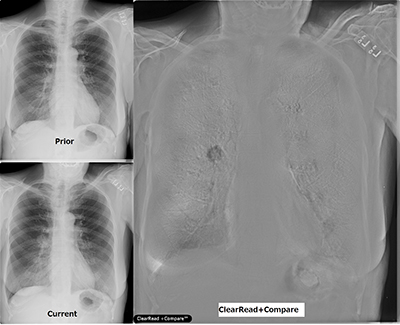

「胸部X線骨組織透過テクノロジー」コーナー

発売以来大きな反響をいただいているClearReadシリーズ。先進の画像処理技術で院内胸部X線読影を強力に支援します。通常撮影で得られる元画像1枚から骨組織透過処理を行う胸部X線骨組織透過ソリューション“ClearRead BS”に加え,さらなる画像処理技術としてメーカや装置を越え,骨組織透過後に経時差分処理を行う“ClearRead +Compare”及び医療用チューブ強調処理技術“ClearRead +Confirm”を紹介します。

ネットワークをベースにしたコンピュータ資源の効率的な利用を目的としたクラウドは医用業界でも大きな注目を集めています。クラウド・ソリューションとして,胸部X線骨組織透過ソリューションClearReadシリーズ,および同一患者の複数検査において同一部位の位置を検出するDICOMボリュームレジストレーションを紹介します。

- 胸部X線骨組織透過ソリューション“ClearRead”シリーズ